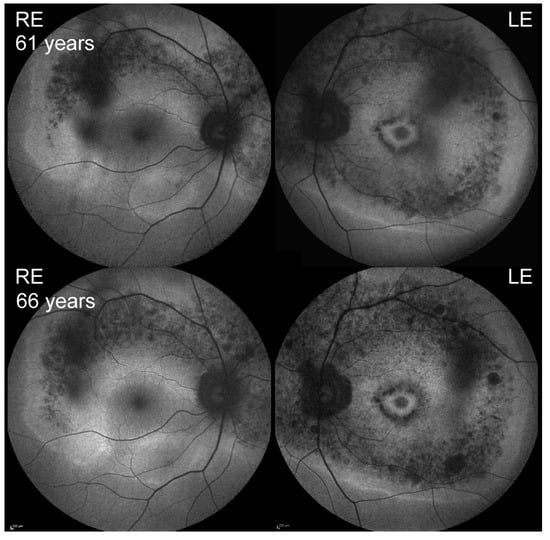

| 3 | p.Trp3955Ter, p.Gly4032Arg | F | 61 | 58 | 1.0, 1.0 | cone-rod dystrophy | 31, 40 (65) |